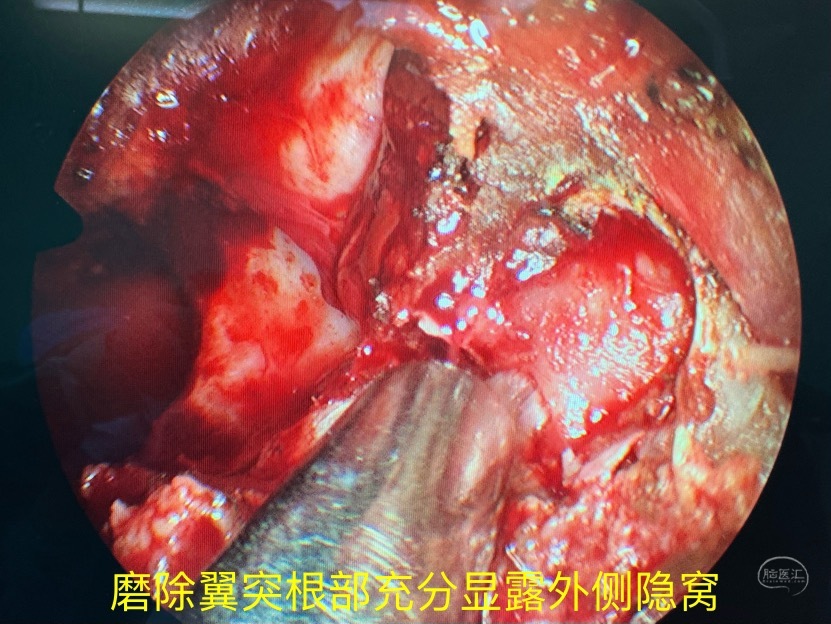

磨除翼突根部充分显露外侧隐窝